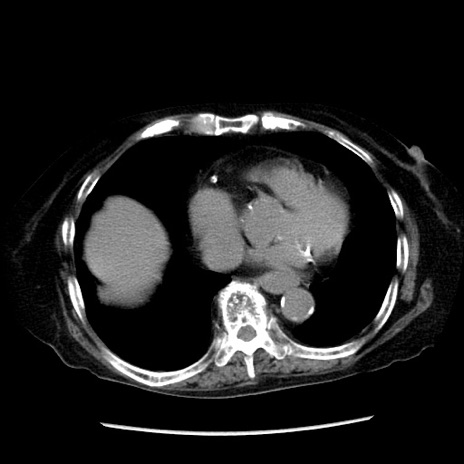

冠状断像